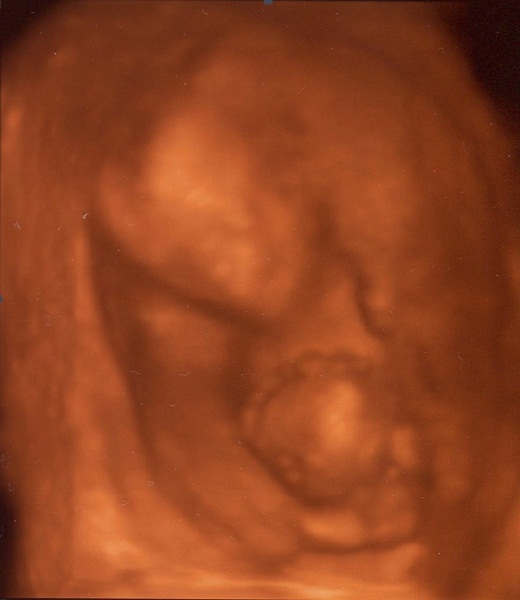

A mostani uh persze saját kérésre volt, ez nálunk most 10.000 Ft. Ebben benne volt a DVD, egy fotó és egy édes plüss maci. (Ez utóbbit csak májusban adták a vizsgálathoz, gyereknapi ajándékként.)